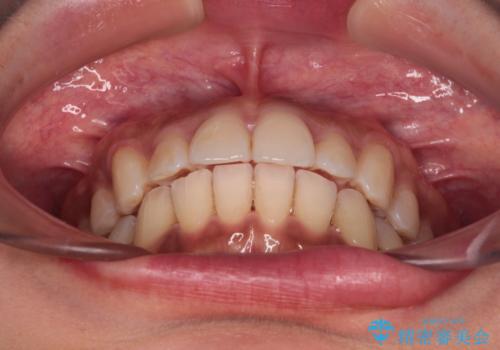

- 全体的な歯列の叢生を気にして来院された患者様です。

奥歯の咬み合わせを見ると、片方は上顎が下顎に対して相対的に前方にある状態でした。

咬み合わせを改善するためには、上顎臼歯を後方に移動させた咬み合わせにする必要があります。

インビザライン単体で改善することも可能ですが、ディープバイトのためインビザライン単体で達成する可能性が低いと考えられたため、カリエール・ディスタライザーという補助装置を併用して、より確実性を上げることとしました。

奥歯の咬み合わせ改善後に、インビザラインにて歯列を整えることとしました。

カリエールディスタライザーを併用したことで、確実かつ短期間で治療を終えることができました。